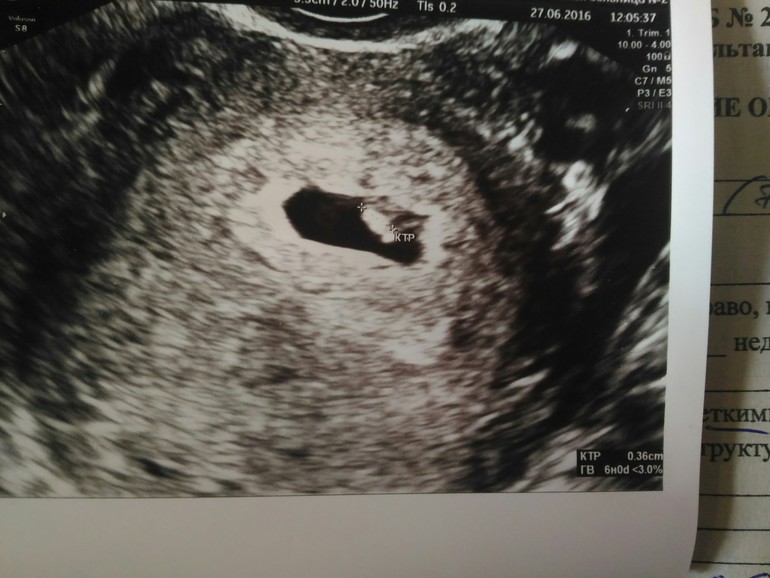

УЗИ!!Девочки у нас все хорошо☺

Беременность- 1 триместр ( только до 10 недель)Эмбрион на 6 недель, сердечко бьется.В общем все прекрасно сказали, на скрининг сразу записали на август. Спасибо вам за поддержку😘, девочки без вас бы я сошла с ума.Теперь могу расслабиться😃

Ой тоже была на Узи 6 нед и 4 дня))) Только у меня мааасенького человечка видно было)_)) Будто на мотоцикле сидит))